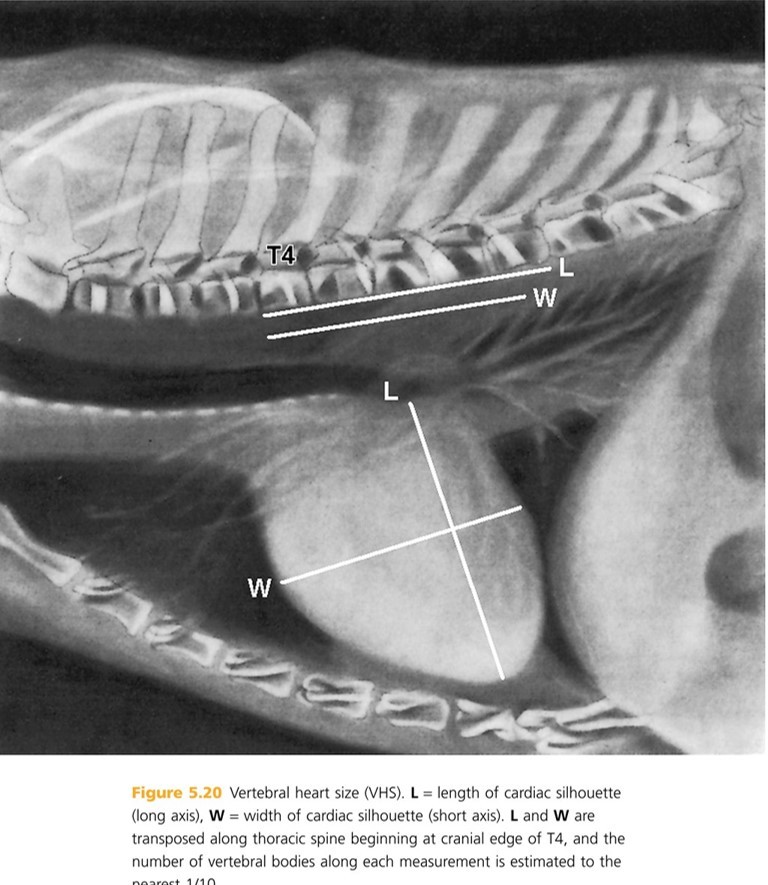

Cardiac division. The Long Axis line (cardiac length) extends from the ____ ____ to the ___ ___., dividing the heart into right chambers cranially and left chambers caudally (Generally in a 3:2 ratio). The Short Axis line (cardiac width) is perpendicular to the long axis at the level of the caudal vena cava and divides the heart into ____ dorsally and _____ ventrally.

tracheal bifucation to the cardiac apex

atria ventricles